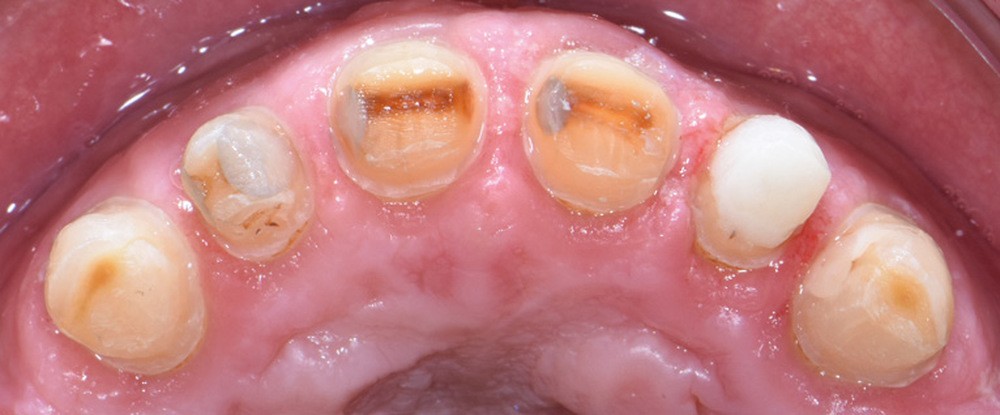

Au vu du contexte para-fonctionnel et de l’étendue de la perte tissulaire, des coiffes périphériques minimalement invasives ont été choisies afin de restaurer l’esthétique et la fonction. Actuellement, aucun consensus n’est fait sur le choix du matériau d’infrastructure à privilégier. Les matériaux hybrides usinables présentent des propriétés mécaniques, physiques et biologiques intéressantes en contexte d’usure sévère (e.g., module d’élasticité, résistance à la propagation de fêlures, facilité de réintervention). Une réhabilitation globale avec remontée de dimension verticale d’occlusion (DVO) par l’intermédiaire de coiffes composites renforcés en nano-céramiques est décrite.